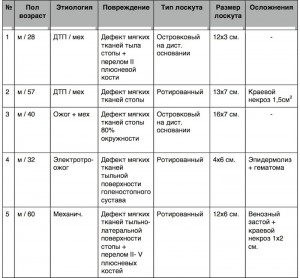

В нашей клинике было выполнено 5 операций с использованием латеральных надлодыжечных кожно–фасциальных лоскутов, характеристика которых представлена в таблице 1 и иллюстрирована клиническим случаем из практики.

Таблица 1.

Характеристика выполненных латеральных надлодыжечных кожно-фасциальных лоскутов

Все лоскуты выжили, пациенты выздоровели и были выписаны из клиники. В результате проведенного лечения восстановлена анатомическая целостность и функция стопы. В качестве осложнений, у 5 пациентов с пластикой латеральным надлодыжечным лоскутом нами наблюдались: послеоперационный отек ротированного лоскута, нарастающий до 3 суток – во всех случаях; венозный застой на ограниченном участке до 1/4 площади лоскута с последующим краевым некрозом 1х2 см. – в одном случае; краевой некроз до 1 см2- – в одном случае; гематома с имбибицией лоскута и лизисом поверхностных слоев кожи вследствие инфекционной атаки – в одном случае.